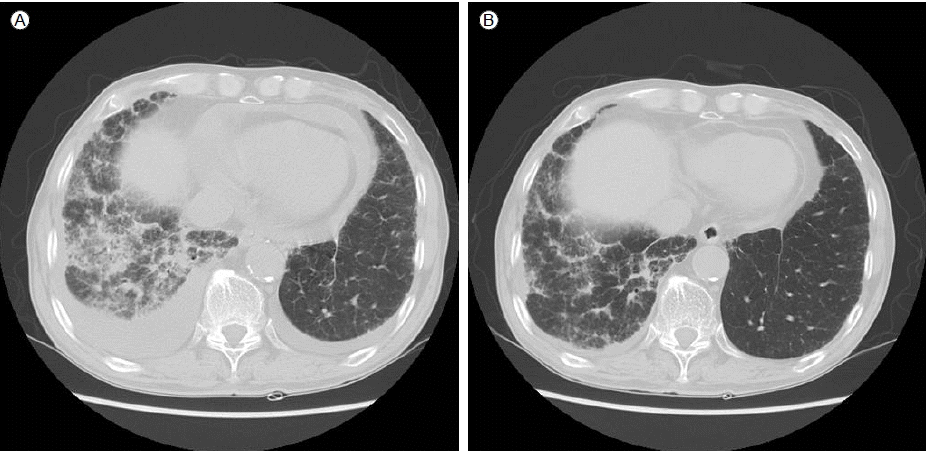

Figure 2.

Chest CT before treatment shows (A) a right dominant pleural effusion and a pericardial effusion. Irregular infiltration in the right lower lobe is noted. (B) At follow-up, both the pleural and pericardial effusions had resolved as had the infiltration in the right lower lobe.

일주일 뒤 환자는 호흡곤란이 더욱 악화되었는데, 흉부방사선 사진에서 둔해진 양측 갈비가로막각은 그대로였고, 심장의 왼쪽 경계는 이전과 비교하여 볼록해졌다(Fig. 1A). 흉부 전산화단층촬영을 시행하였다. 우측으로 더 많은 양의 흉수가 관찰되었고, 심장막액도 관찰되었다. 우측 하엽으로 망상형의 불규칙한 병변이 보이는데, 이전에도 우하엽의 병변은 관찰되고 있었으나 병변의 범위와 정도가 더 악화되었다(Fig. 2A). 이어 시행한 심장 초음파 검사에서 중등도 이상의 심장막액을 확인하였고, 심장눌림증의 소견은 보이지 않았으나 진단 및 치료의 목적으로 심장막 천자를 시행하였다. 추가 검사를 위해 흉수 천자와 말초혈액 채취도 다시 시행하였다. 환자의 혈청 류마티스인자가 119 IU/mL으로 상승하였으며, 흉수에서는 130 IU/mL 이상, 심낭액에서도 31 IU/mL으로 상승해 있었다(Table 1). 혈청과 흉수의 항핵항체(anti-nuclear antibody)는 1:40이었고, 이외에 혈청 항중성구세포질항체(anti-neutrophil cytoplamic antibody), 항Ro항체(anti-Ro antibody), 항La항체(anti-La antibody), Anti Scl 70 antibody도 음성이었다. 흉수와 심장막액은 모두 삼출성 성분이었고, 결핵이나 악성종양의 증거는 없었다. 기관지내시경을 통한 세척액 검사에서도 결핵균이나 이상 세포는 관찰되지 않았다.

류마티스성 흉막염과 심장막염이 발생하여 환자의 호흡곤란이 악화된 것으로 판단하고 프레드니솔론 0.5 mg/kg을 하루 한번 투여하기 시작하였다. 치료 시작 일주일 후 환자는 호흡곤란이 호전되었고, 프레드니솔론을 유지하면서 퇴원하였다. 4주 후 시행한 흉부방사선 사진에서는 치료 전과 비교하여 흉수가 감소한 소견을 보였고(Fig. 1B), 2개월 후 추적검사한 흉부 방사선단층촬영에서도 양측의 흉수가 거의 소실되고, 심장막액도 감소한 모습이 관찰되었다. 더불어 우하엽의 병변도 치료 전보다 호전되었다(Fig. 2B). 환자는 이후 6개월 동안 증상악화 없이 스테로이드 감량하며 경과관찰 중이다.